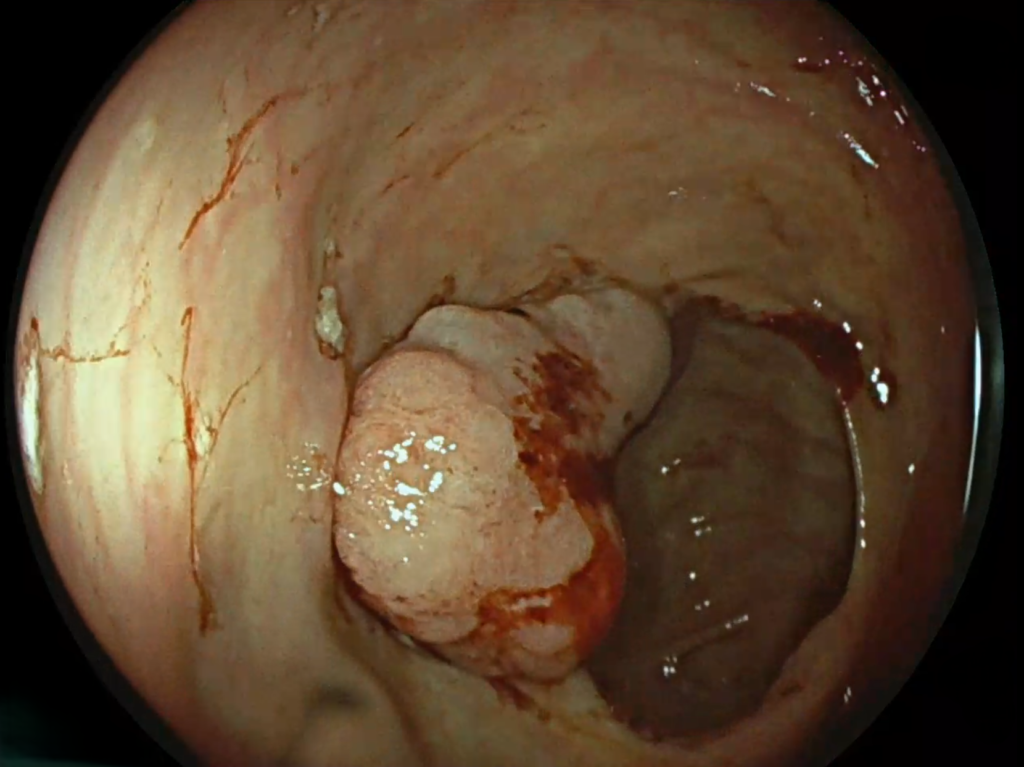

Prin monitorizarea constantă cardiavasculară, dr. Carmen Roxana Ionașcu-Fometescu, medic primar cardiologie, a observat semnele unei anemii feriprive și a solicitat o evaluare gastroenterologică. Investigațiile efectuate de dr. David Marica, specialist gastroenterolog au dus la diagnosticul de cancer colonic, ceea ce a impus o intervenție chirurgicală.

Inițial, evoluția postoperatorie a fost favorabilă. Totuși, pacientul a dezvoltat o hemoragie digestivă inferioară, gestionată prompt prin hemostază endoscopică de urgență de către dr. David Marica, în contextual nevoii constante de hemodializă.